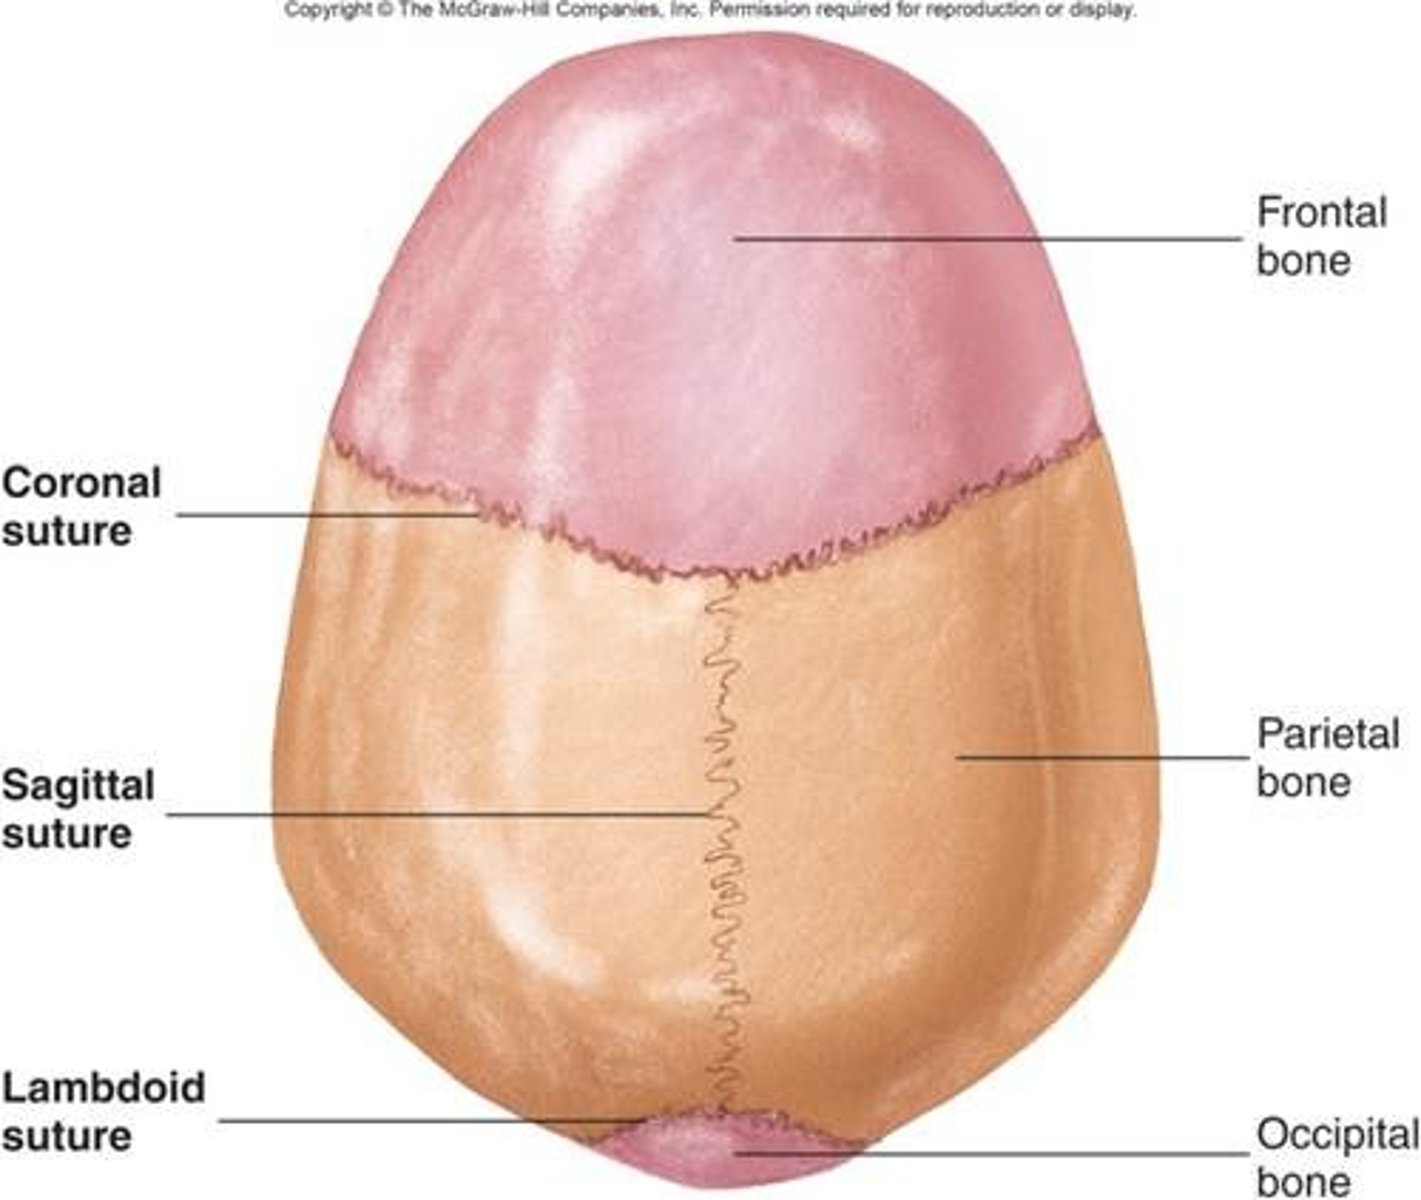

Types of fibrous joints

-suture

-gomphoses

-syndesmoses

Fibrous joints

consists of inflexible layers of dense connective tissue, holds the bones tightly together

-solid joints

Sutures

occurs only in the skull where adjacent bones are linked by a thin layer of connective tissue

Sutural ligament

thin layer of dense connective tissue that joins flat bones of the skull together